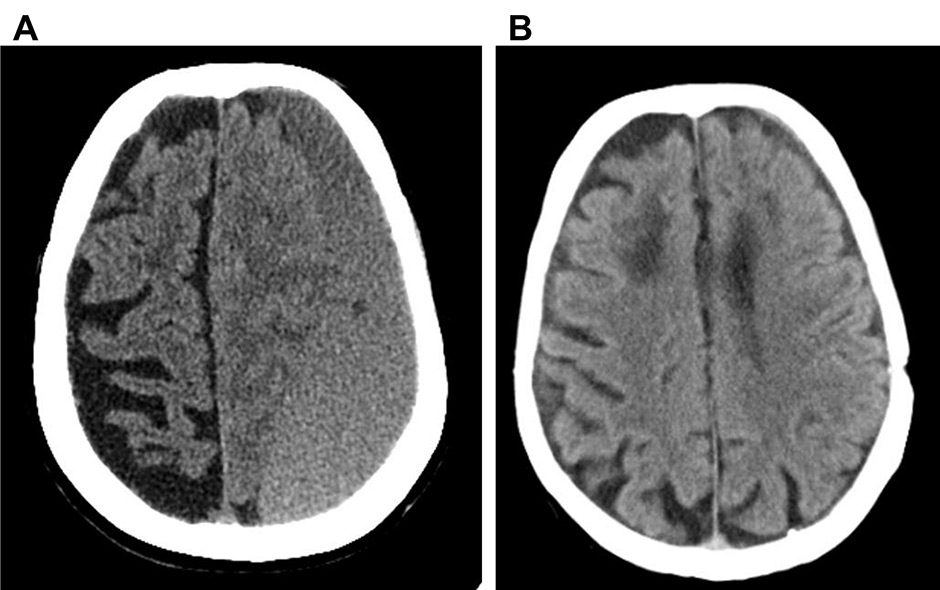

Figure 1

Representative CT scan image of a left fronto-temporo-parietal-occipital cSDH, before surgery (A) and after three month-follow-up during apixaban treatment (B).